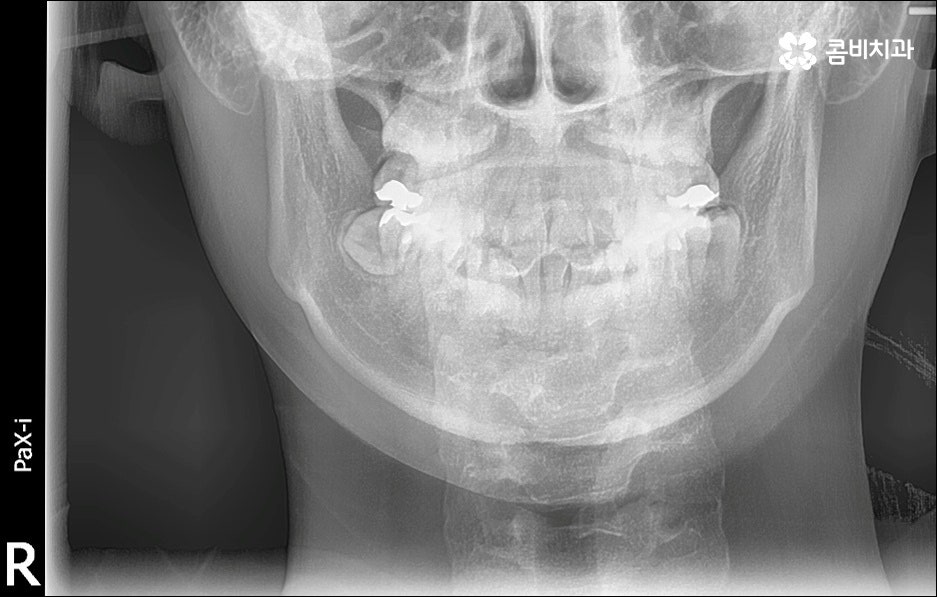

앞니가 튀어나오는 원인은 무엇일까요? 앞니 돌출 의 원인은 치아 크기가 큰 데 반해서 골격이 많이 작거나 상하악골 크기 차이가 많이 나는 것처럼 유전적인 요소에 기인하는 경우가 많으나 후천적인 생활 습관으로 인해서 발생하고 강화될 수도 있기 때문에 주의하실 필요가 있어요. 예를 들어 어릴 때 부터 손톱을 물어뜯거나 손가락을 자주 빠는 습관, 혀로 앞니를 밀면서 빼물곤 하는 습관을 가지고 있었다면 이로 인해 앞니가 튀어나올 수도 있는 거예요. 또한 축농증, 비염 등의 질환으로 인해 구호흡을 하게 되었다면 이것이 원인으로 작용할 수도 있으니 필요하다면 이비인후과와 협진을 하는 등 원인파악과 개선을 전반적으로 함께하시길 권유드리고 있어요.

만약에 앞니 돌출 이 각도만의 문제라면 이를 교정하기 위한 치료는 좀 더 간단하게 끝날 수 있습니다. 말씀드렸던 것처럼 상황에 따라 보다 빠른 부분교정을 통해 앞니만 교정 치료를 진행할 수도 있을 거예요.

하지만 보통은 돌출된 앞니 뿐 만 아니라 골격적인 부분이 원인이 되는 경우가 많으며 이런 경우에는 상태에 맞게 전체적으로 교정을 진행하여야 교합이 올바르게 되고 입매가 전체적으로 균형감 있게 개선될 수 있어요. 이런 경우에 골격적인 원인을 무시한 채 무리하게 치아의 각도만 안쪽으로 넣으려고 하면 자칫 옥니가 될 수도 있기 때문에 이러한 부작용을 막기 위해서도 환자분들의 상황을 정확하게 검진하고 그에 맞는 교정 플랜을 세우는 것이 필요한 거예요. 물론 부정교합 정도가 심각하고 골격적인 원인이 이미 굳어진 경우와 같이 수술이 함께 필요한 케이스도 있을 수 있으나 교정 치료만으로도 튀어나온 앞니가 들어가면서 자연스럽고 부드러운 인상으로 바뀌는 경우도 많으니 먼저 검진과 상담부터 꼼꼼하게 진행해 보시길 권유드리고 있습니다. 특히 개개인의 치열, 교합, 잇몸 상태, 구강구조 등을 면밀하게 파악하고 그에 따른 정확한 치료 계획을 수립할 수 있는 경험 많은 의료진과 함께 하는 것이 중요할 수 있어요.